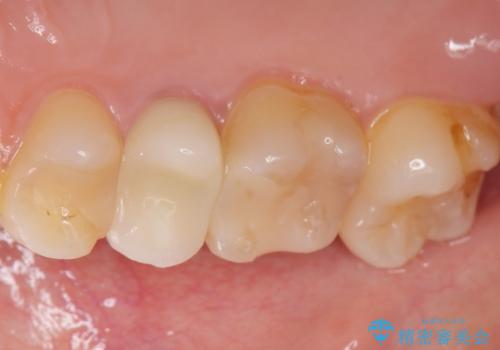

差し歯をもっと自然に 30代女性

- もっと自然にみえるような差し歯にしたいと希望され来院された患者様です。

患者様の天然歯はグラデーションがあり切縁(歯冠の先端)はやや透けていて透明感があるのに対し、前歯(右上1)の差し歯はやや黄色く不透明で単調な色味でした。

患者様のご希望により、右上1はジルコニアクラウン(スペシャル)、右上5はジルコニアクラウン(スタンダード)へやりかえることにしました。

前歯のクラウンは一度修正し、患者様の理想とする色味や形態を追求しました。

天然歯と見紛うほどの自然な仕上がりに喜んで頂けました。

右上1:ジルコニアクラウン スペシャル

右上5:ジルコニアクラウン スタンダード